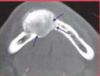

What is the radiographical finding?

Odontogenic

Keratocyst

OKC